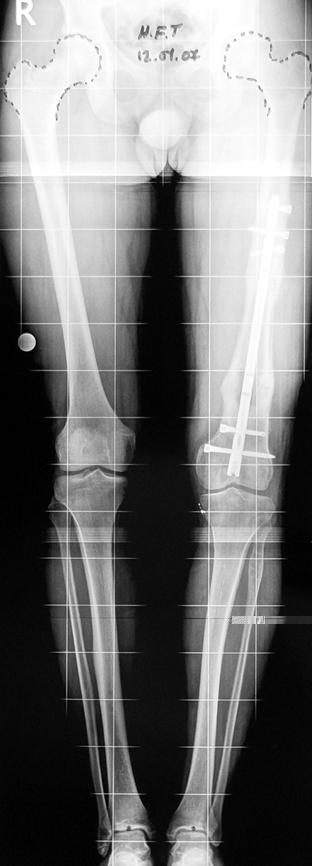

Bu Bacak Kısalık tipi bir kırığın kısalmış pozisyonda kaynaması ile oluşur. Bir çok vaka yetişkinlerde görülür ve sadece bir uzatma ile tedavi edilebilir. Ek deformiteler de aynı anda düzeltilebilir. Bu hastaların çoğu çivi üzerinden uzatma veya tam implante edilen çivi ile tedavi edilebilirler.